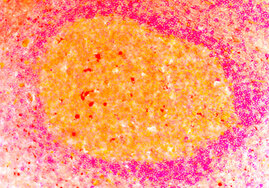

Immunzellen aus dem Gewebe menschlicher Tonsillen dienten LMU-Wissenschaftlern zur Entwicklung eines Verfahrens, mit dem sich wichtige Schritte der…